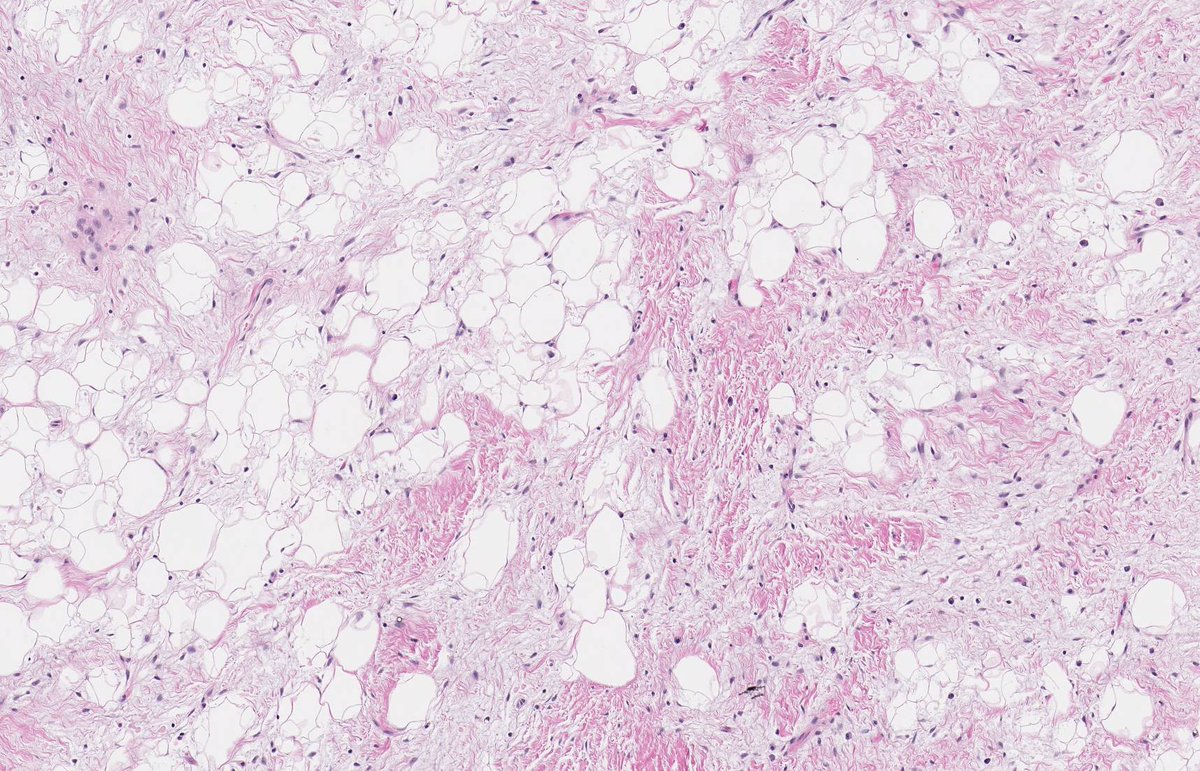

PERINEPHRIC MYXOID PSEUDOTUMOUR OF FAT. NB: sheets of mature adipocytes; spindle-stellate cells in myxoid stroma; mild chronic inflammatory infiltrate; MDM2 non-amp; may arise in context of renal cell disease and transplantation (PMID: 19525929, 30826321, 33835530).